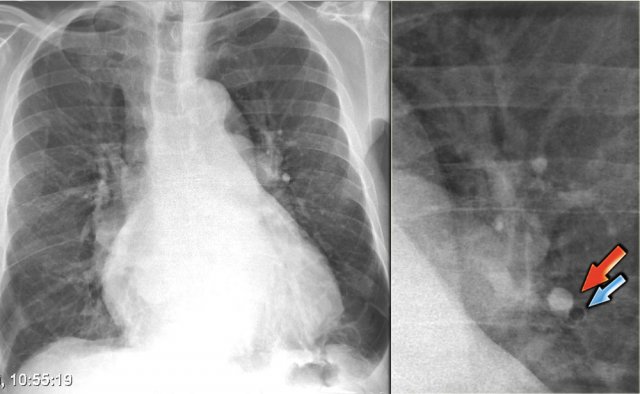

On the left a patient who was admitted with severe dyspnoe due to acute heart failure.

The following signs indicate heart failure: alveolar edema with perihilar consolidations and air bronchograms (yellow arrows); pleural fluid (blue arrow); prominent azygos vein and increased width of the vascular pedicle (red arrow) and an enlarged cardiac silhouette (arrow heads).

After treatment we can still see an enlarged cardiac silhouette, pleural fluid and redistribution of the pulmonary blood flow, but the edema has resolved.